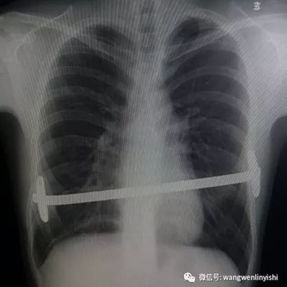

Incisions were made along the previous surgical scars on both sides of the chest wall to remove the bars placed during the Nuss procedure. Then, the cyst on the left anterior chest wall was explored and incised through the incision on the left side of the chest wall, and the contents of the abscess were thoroughly debrided. A third incision along the midline scar allowed careful pre-shaping of the depressed bony structure of the anterior chest wall. Two bars were then implanted to complete the Wung procedure. Postoperatively, the chest wall appearance was restored to normal.

2. Improper bar Placement and Positioning: Preoperative imaging reveals that the bar was positioned along the upper edge of the groove-like depression and was placed at an angle.For optimal support and effective correction of the depressed bony structure, the bar should have been positioned at the base of the depression.

3. Insufficient Number of Bars: In adult patients, the larger chest wall depression and increased bone density generally necessitate the use of at least two bars during corrective surgeries to ensure adequate support and achieve the desired outcome. However, only one bar was used in the patient’s initial surgery, which was insufficient to effectively correct the depression.